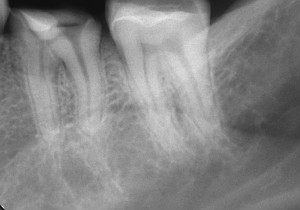

↑before ↑after

では、感染根管処置はどうかというと通常の根管治療だけで経過良好な現在生存している歯は、90%。